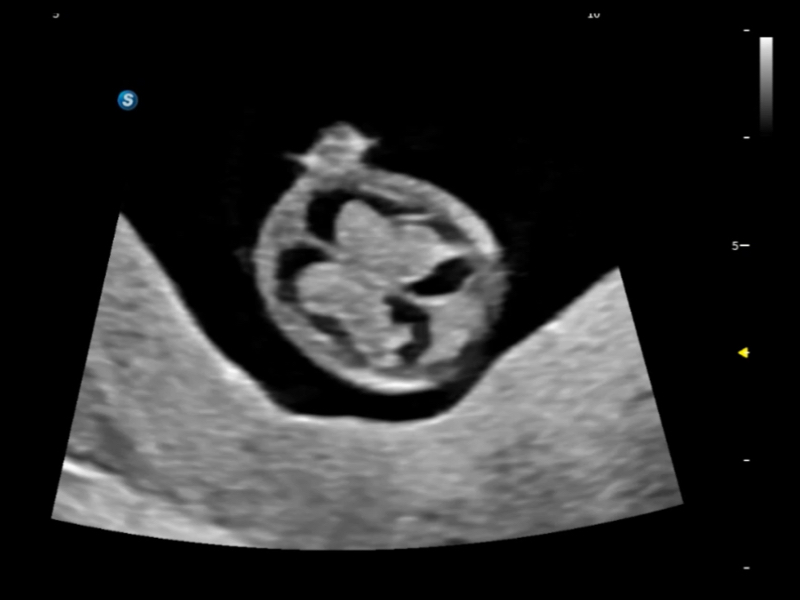

作為開(kāi)立醫(yī)療全新打造的超高端旗艦超聲產(chǎn)品,從探頭抬起喚醒開(kāi)啟掃查到多維探頭發(fā)射接收,通過(guò)先進(jìn)的場(chǎng)成像發(fā)射、自適應(yīng)聚合重建等技術(shù),基于RF Data原始射頻數(shù)據(jù)在圖像生成、高端功能等方面實(shí)現(xiàn)突破,為婦產(chǎn)科、兒科提供全方位臨床解決方案。

夢(mèng)溪?P80以“關(guān)愛(ài)女性”為基石,提供全方位的解決方案,量身定制以滿(mǎn)足女性的健康需求,涵蓋婦科、生殖健康檢查、產(chǎn)前篩查及產(chǎn)后康復(fù)等領(lǐng)域。